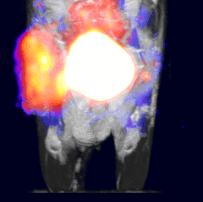

Above: C57BL/6 mouse bearing a C3 (cervical cancer) flank tumor injected with approximately 17.5 MBq of 18F-FDG. Left to Right: MIP, Coronal, Sagittal, and Axial views. Images courtesy BIOTIC.